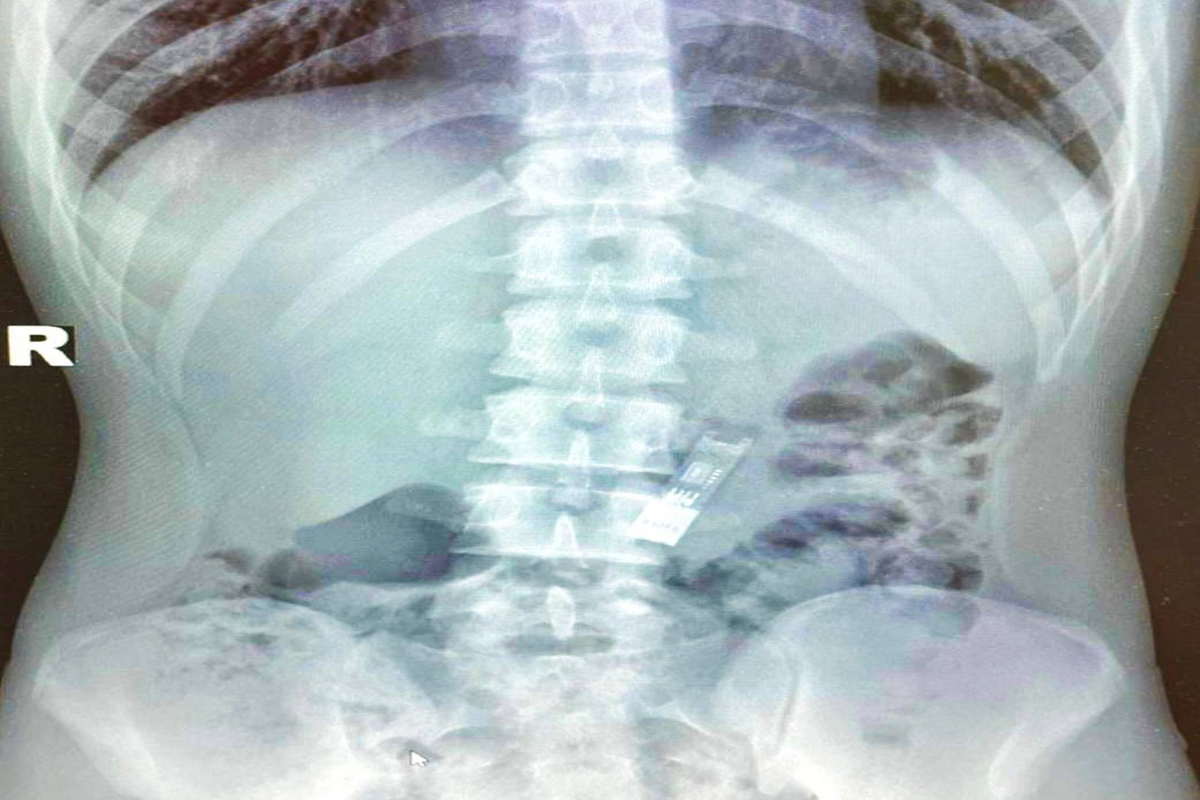

Необычный случай произошел с 16-летним школьником из Подмосковья — он случайно проглотил флешку, на которой хранилось его домашнее задание по информатике. В результате подросток оказался в Детском клиническом центре имени Л. М. Рошаля, где врачи успешно извлекли носитель. Об этом сообщили в Министерстве здравоохранения Московской области.

Операция прошла успешно, и уже на следующий день подростка выписали. Врачи отметили, что флешка не повредила его здоровью и даже осталась в рабочем состоянии, благодаря чему школьник смог сдать домашнюю работу без проблем.

Фото: Министерство Здравоохранения Московской области